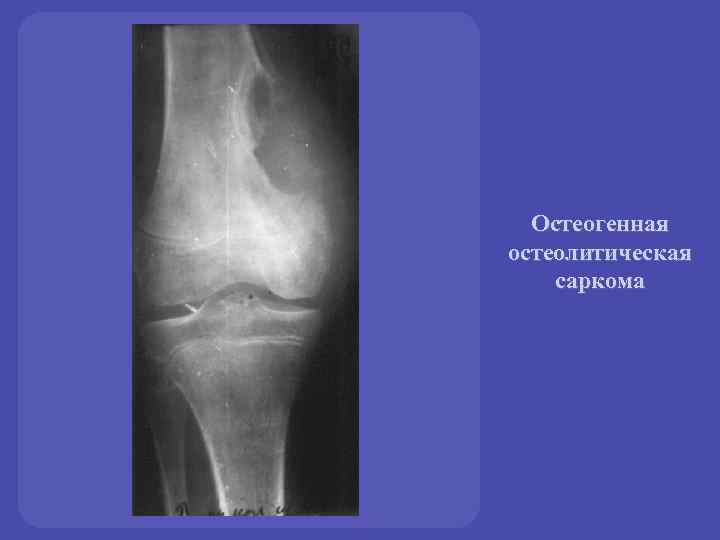

Рентгенологическая картина остеогенной саркомы кости - 98 фото